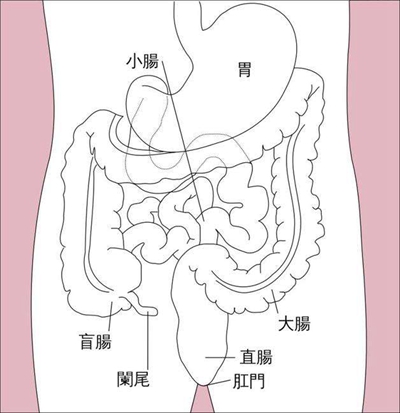

盲腸炎圖片

盲腸的位置 (50)

盲腸的位置 (6)

盲腸的位置 (7)

盲腸的位置 (8)

盲腸的位置 (9)

盲腸的位置 (46)

盲腸的位置 (47)

盲腸的位置 (48)

盲腸的位置 (49)

盲腸的位置 (5)